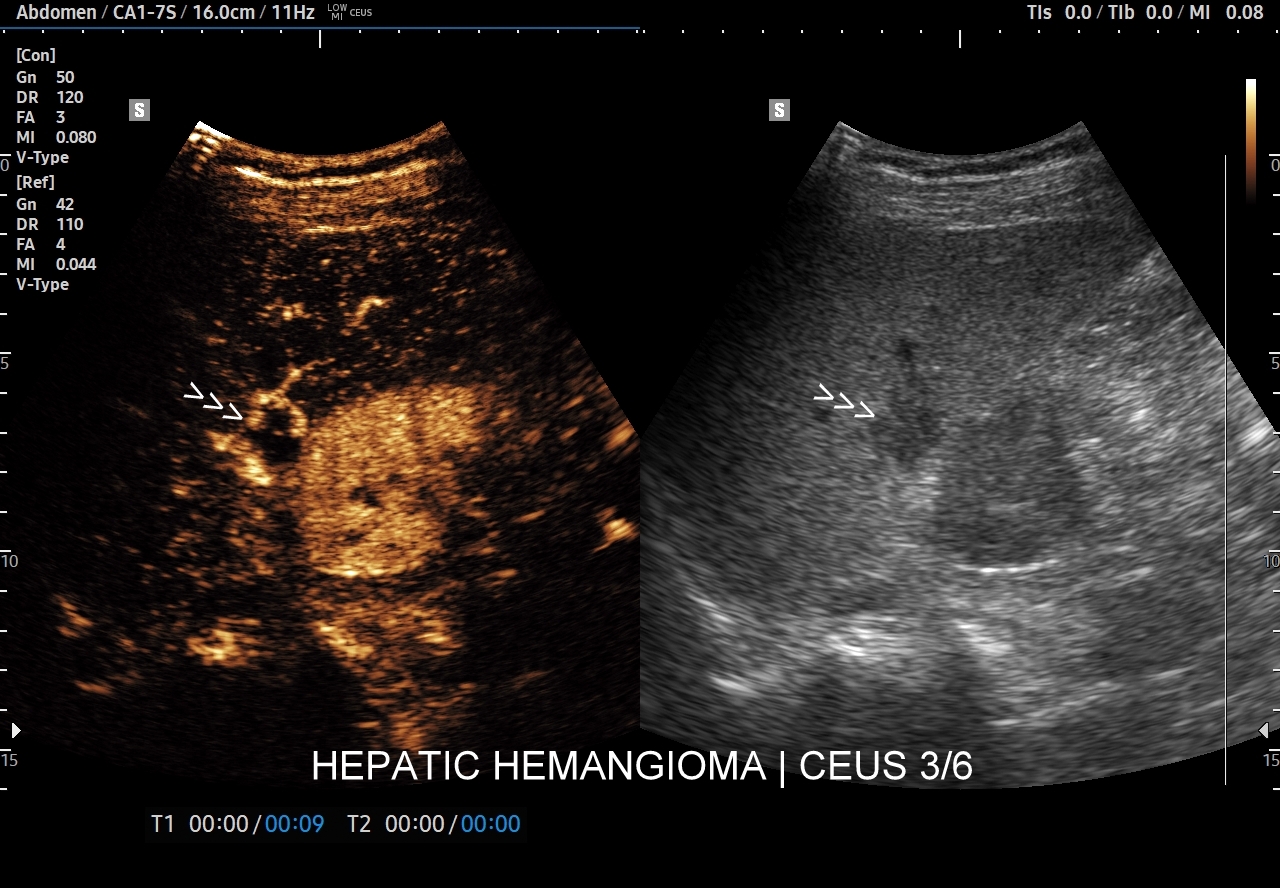

Najbardziej charakterystyczną cechą naczyniaka wątroby w badaniu CEUS jest jego wypełnianie w postaci guzkowej (ang. peripheral nodular enhancement) od obwodu ku centrum zmiany (ang. centripetal). Szybkość wypełniania bywa różnorodna, może być powolna lub szybka. W przypadku szybkiego wypełniania (tzw. flash-filling), w celu wykazania charakterystycznego centrypetalnego wypełniania niezbędna może być postprocessing’owa analiza poklatkowa zapisanego nagrania badania. W fazie późnej naczyniak wątroby pozostaje izowzmocniony lub hyperwzmocniony w stosunku do natywnego miąższu wątroby.

W przypadku dużych naczyniaków obszary, które uległy wykrzepianiu pozostają awaskularne przez wszystkie fazy badania CEUS, tj. nie wypełniają się kontrastem (nonenhancing). W przeciwieństwie do powyższego konstelacja, w której to w fazie wczesnej pojawia się wzmocnienie, a następnie w fazie wrotnej lub późnej ulega wypłukaniu (hypoenhancement) świadczy o cechach złośliwych diagnozowanej zmiany ogniskowej w wątrobie i wyklucza rozpoznanie naczyniaka.